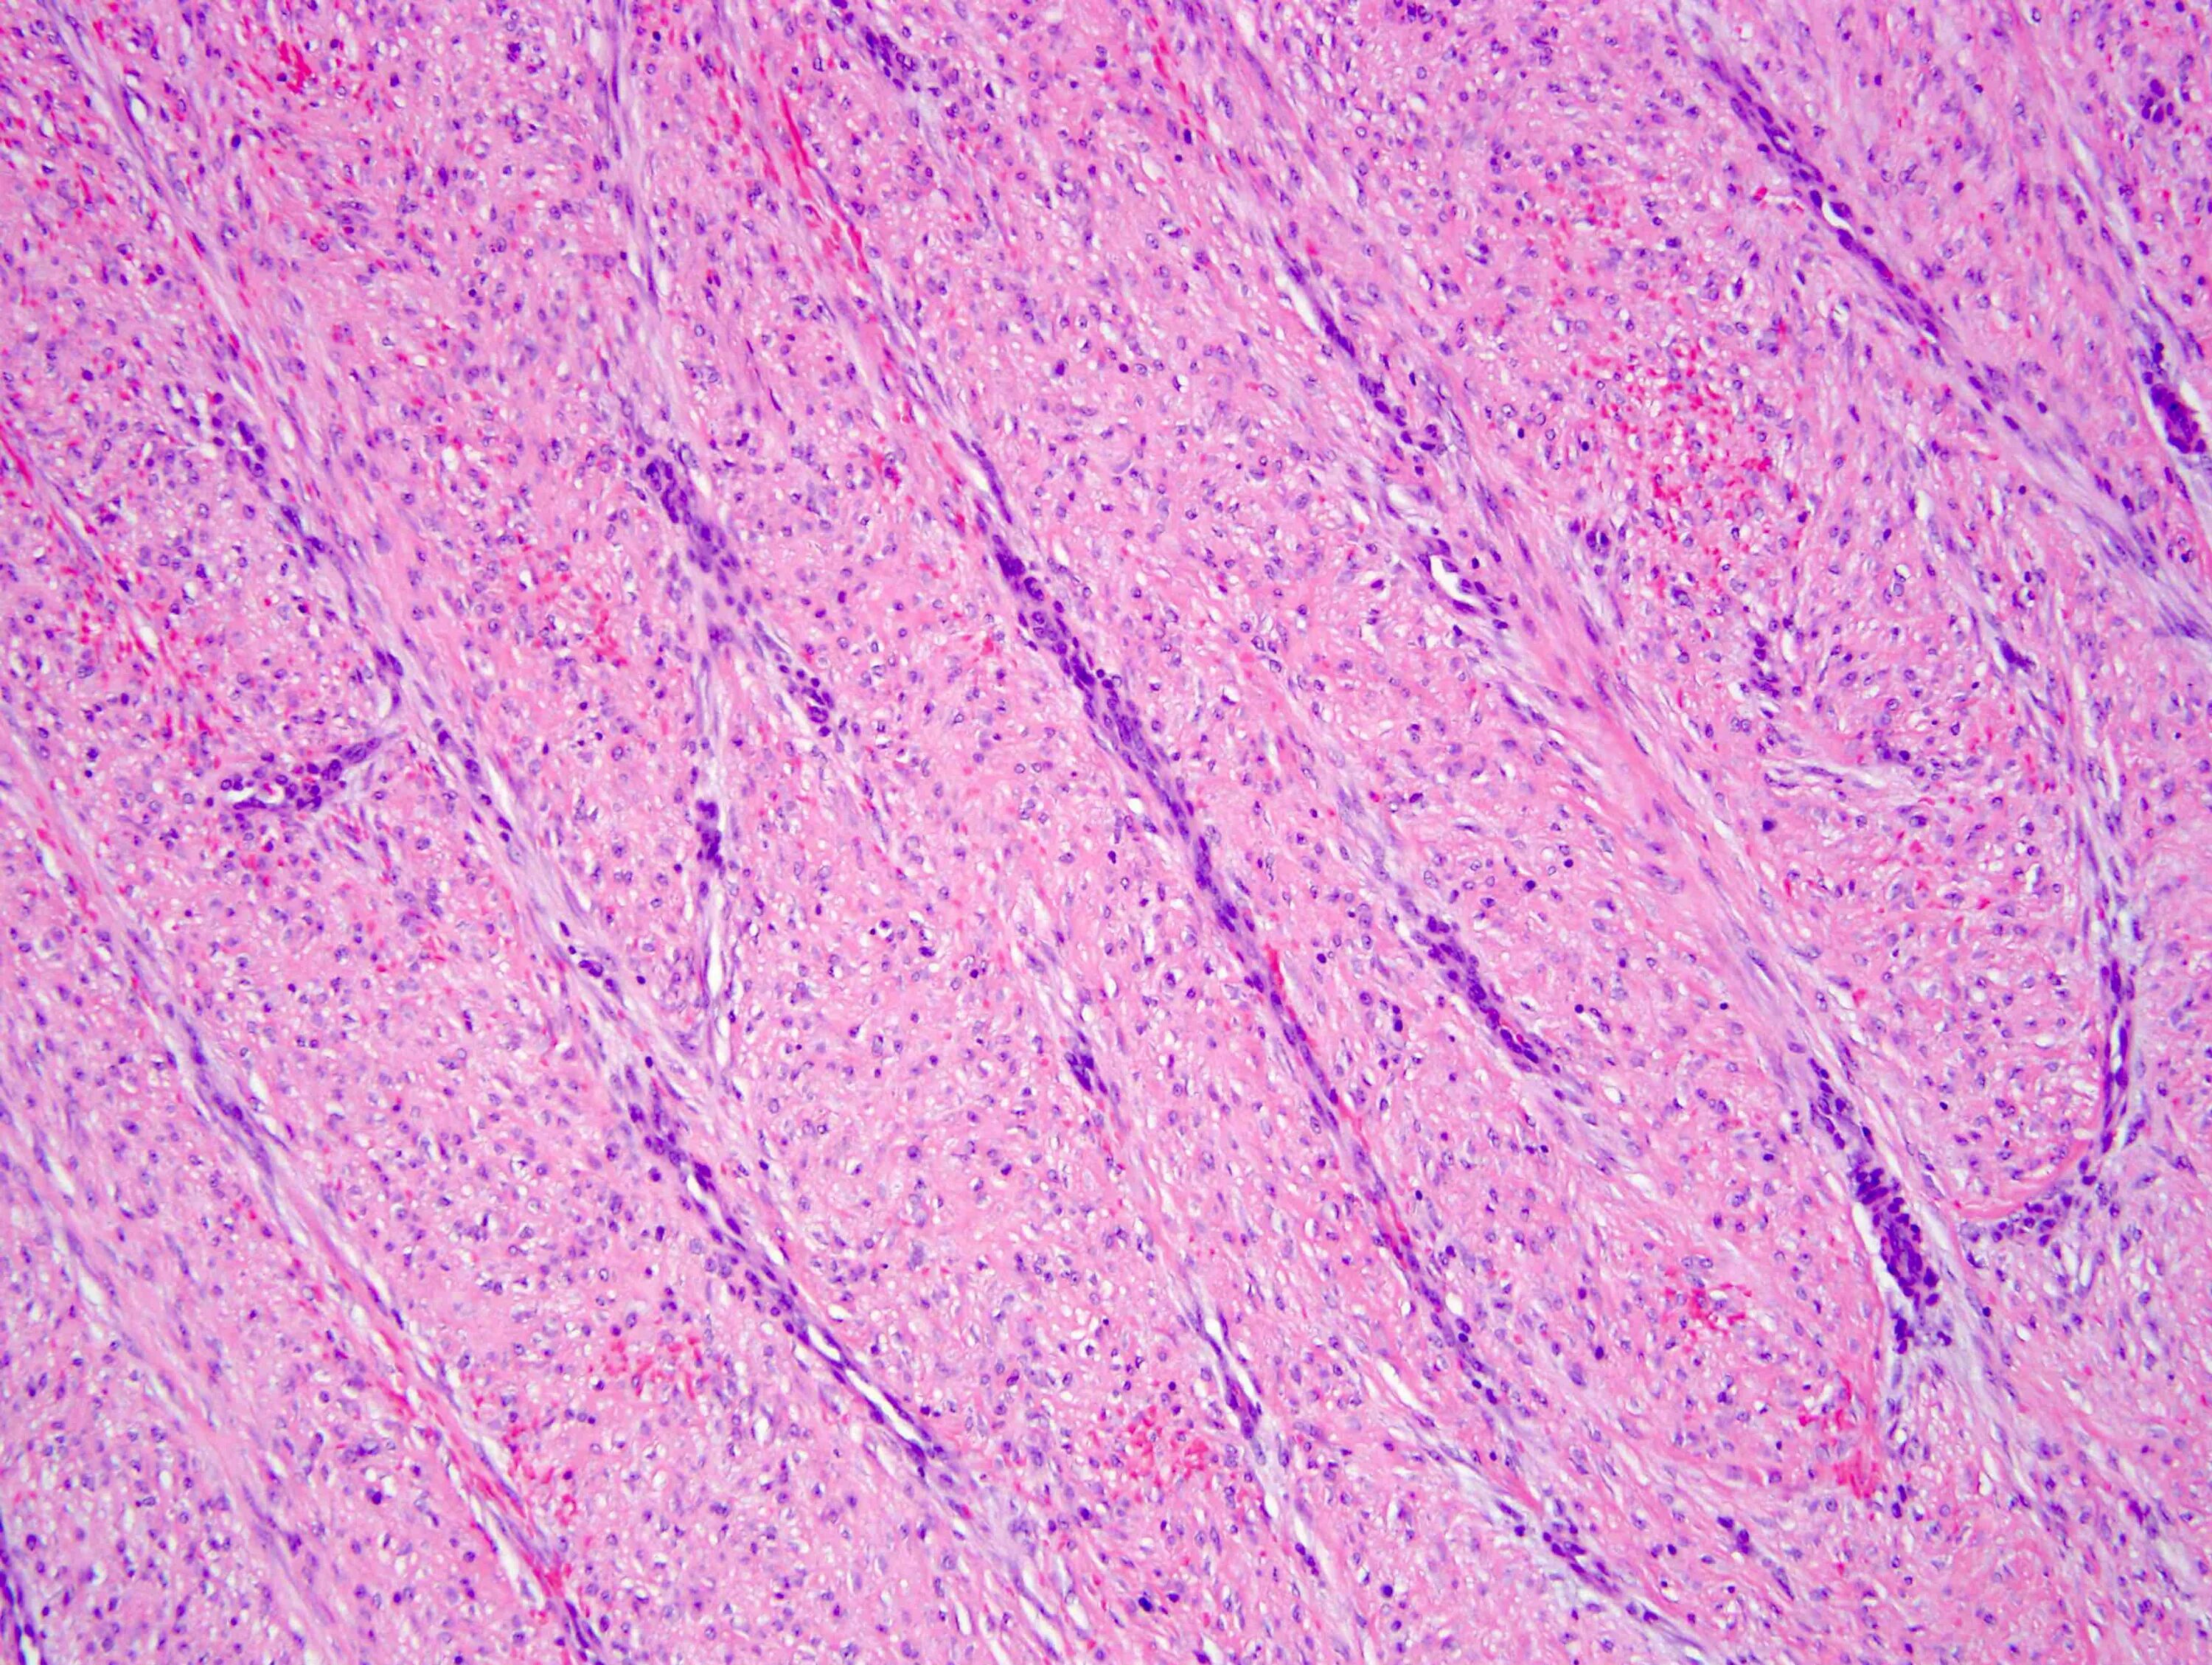

Гистология экология